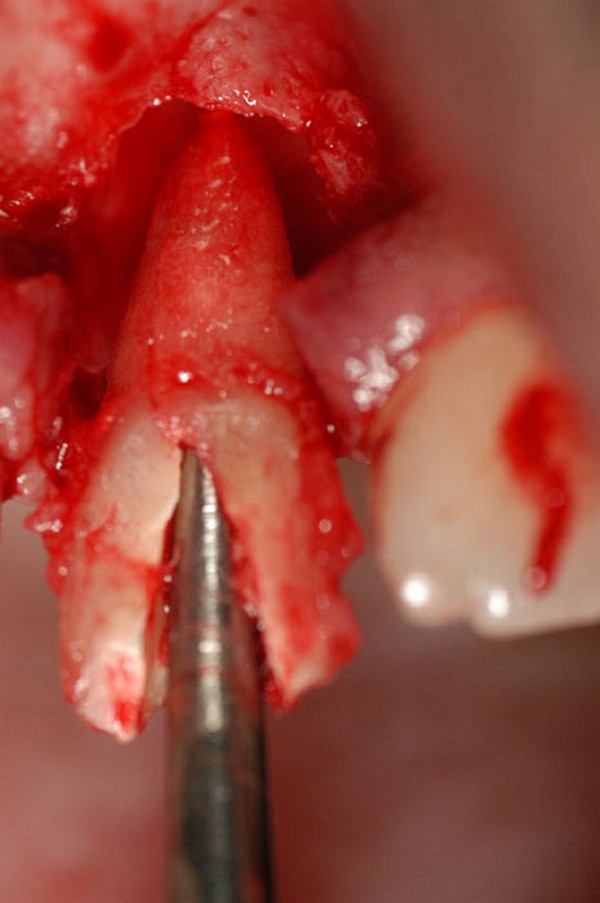

A.I.D.A.(Avulsionador Intradentario Atraumático.)

Fig.15 Fig.16(Pie de foto: A.I.D.A.)

Fig.17(Pie de foto: Preservación de la cresta remanente)